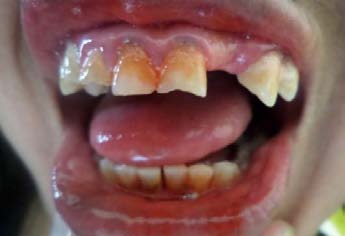

A 20 year-old male patient sought to a private practice with a chief complaint for discoloration and dull pain in maxillary anterior teeth region since 1 year. Clinical examination reveals non vital response of 11, 21. Radio graphically, maxillary left central incisor showed the radiolucency in the middle third of the root surface indicating of internal resoprtion (figure 1). The patient reports he did not remember trauma history in the same region. It was decided to complete the endodontic therapy for 11, 21.